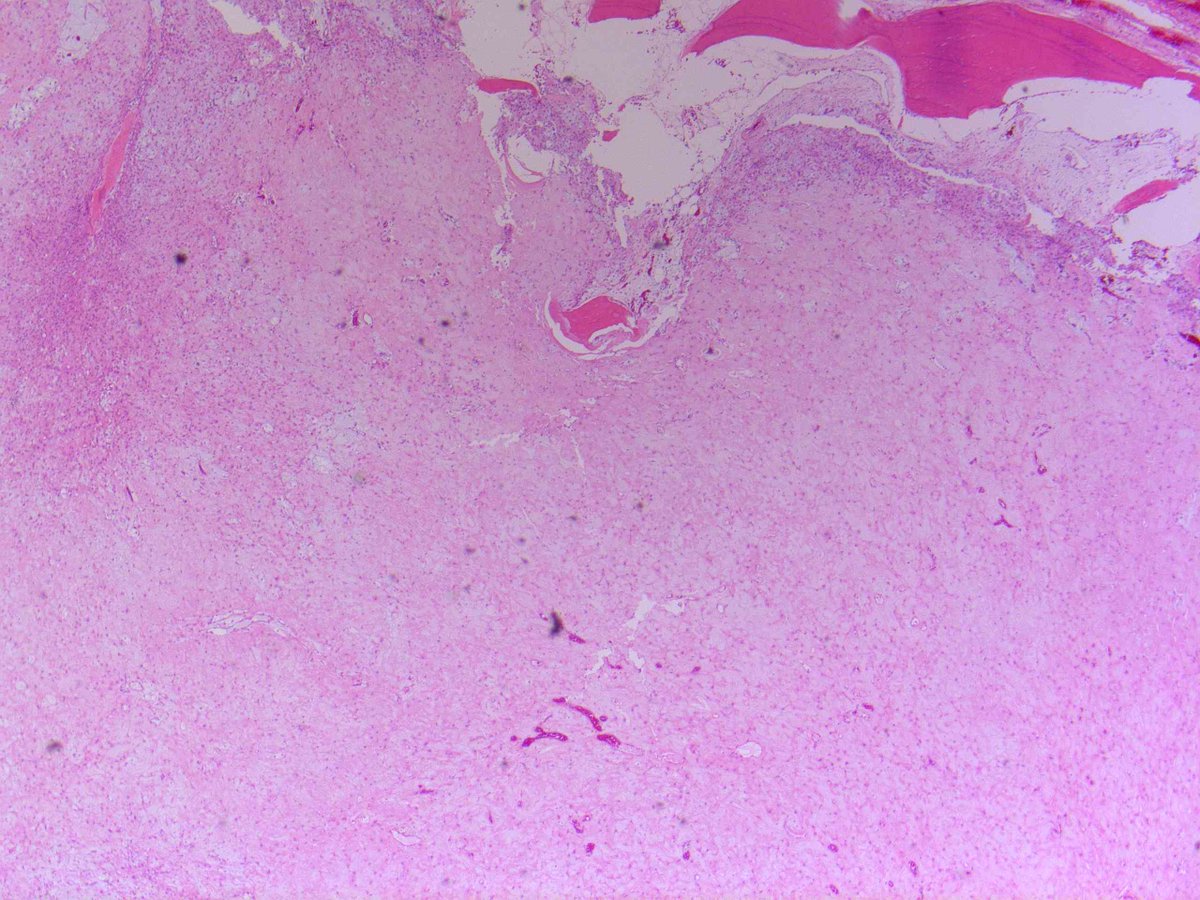

Mesenteric fibromatosis showing cytologically spindle cells in a

Histopathology of Fibromatosis Cases. A Low magnification shows Spindle Cell Fibroma spindle cell lesions can occur in head and neck skin, in the soft tissues of the scalp, orbit, and neck, and along the. Also known as dermatofibroma) is one of the most common cutaneous mesenchymal. Eccentric lytic lesion with sharp,. variant of metaplastic carcinoma with low grade, bland spindle cells histologically resembling fibromatosis. fibrous histiocytoma (fh; One. Spindle Cell Fibroma.